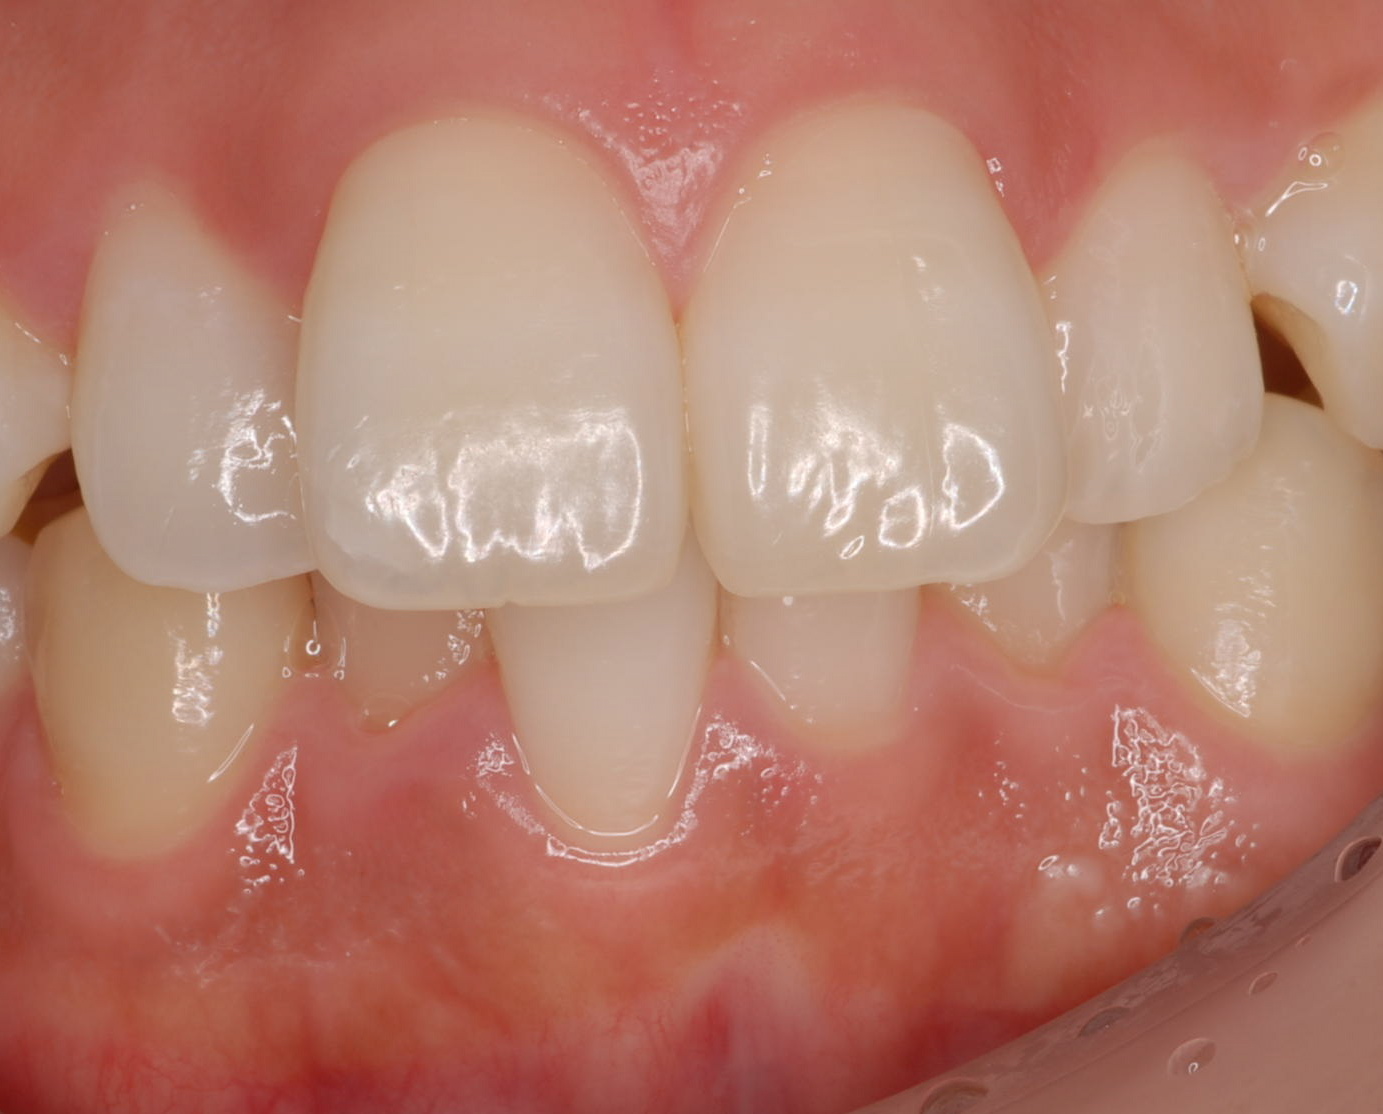

上の左右2番目の歯が内側にたおれているのをきれいにしたいという患者さんでした。

矯正をするか、かぶせで治すか、ということでいろいろ話合い、ラミネートべニアで治療しようということに決まりました。

SET後

ラミネートベニアはもちろんセラミック。

e-MAXです。かなり強度があります。